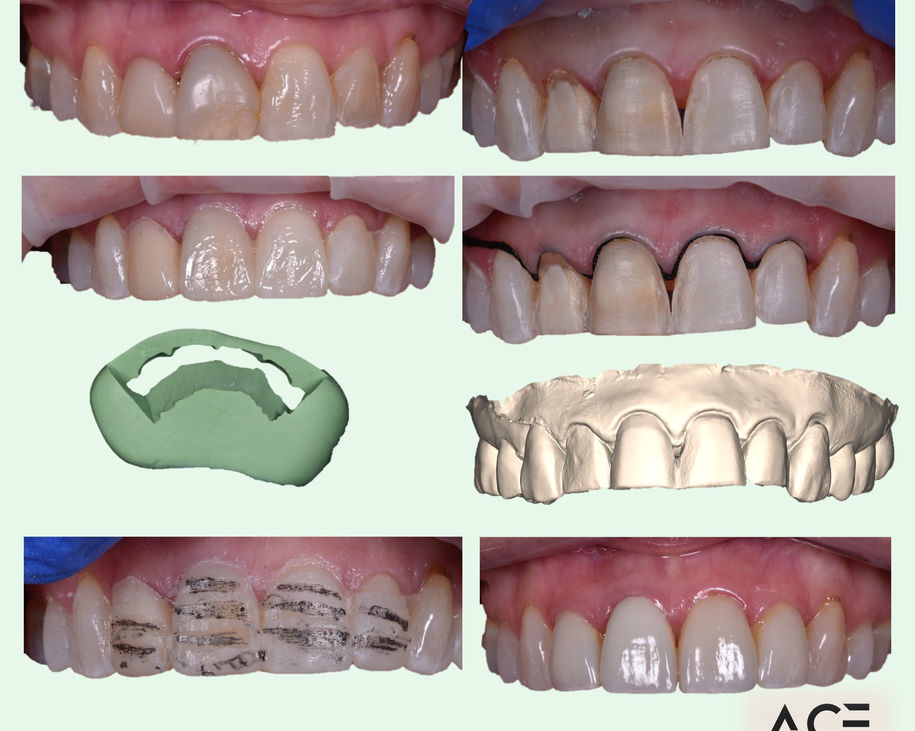

Alumni Outcomes showcasing below snippets of cases submitted as part diploma submissions

Dentists transitioning from routine dentistry into advanced restorative cases

Improved treatment planning confidence

Predictable clinical outcomes through structured protocols